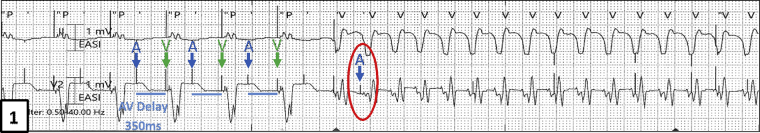

He developed VT at a rate of 163 bpm with a cycle length of 367 ms, as evidenced by the change in morphology seen on the telemetry strip (Figure 1) during his stay and was found unresponsive. Immediate external direct current cardioversion was successful in restoring sinus rhythm. Upon interrogation of his CRT-D, an episode of atrial pacing at a rate of 163 bpm was seen with no antitachycardia therapy delivered from the device (Figure 2A and B). What was the mechanism for the apparent atrial “tracking” of his VT and why was therapy withheld? We further explain in our discussion below.

Telemetry strip showing APVP with prolonged AV delay (350 ms); subsequent change in rhythm and rate indicating ventricular tachycardia. Atrial paced event circled in red indicates the likely inferred “chamber of onset” of ventricular tachycardia as the atrium.